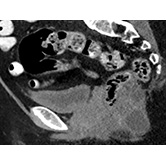

Genitourinary — Adrenal Cortical Neoplasm arising from Ectopic Adrenal Tissue Jamie Crist, MD |

![]() |